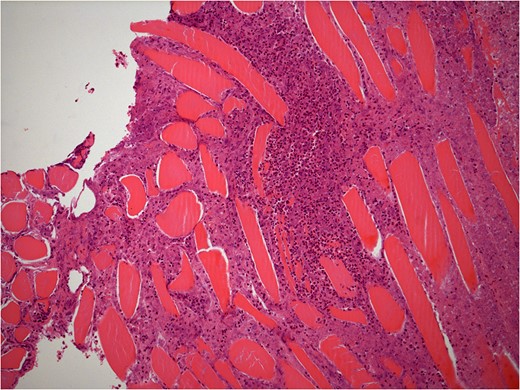

He underwent surgery to explore the tendon where an irregular, cystic, fibrofatty lesion was identified within the tendon (Figs 3–5). This was successfully resected and sent for histology which showed a florid granulomatous and histiocytic response to the suture material, in keeping with a suture granuloma (Figs 6 and 7). There was histological evidence of the abscess extending into the muscle (Fig. 8).